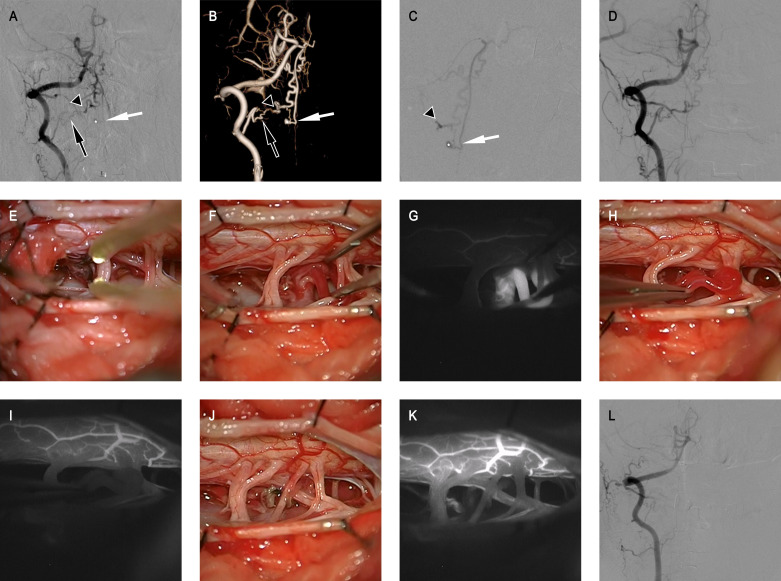

Results: The patients' median age was 56 years (IQR 47-62 years). The majority of patients were men with 166 (83.8%) patients. The most common clinical manifestation was SAH (52.0%), followed by venous hypertensive myelopathy (VHM) (45.5%). The most common CCJ AVFs type was dural AVF, with 132 (63.5%) fistulas. The most frequent fistula location was C-1 (68.7%) and dural branch of vertebral artery (70.2%) was the most involved arterial feeders for fistulas. The most common direction of venous drainage was descending intradural drainage (40.9%), followed by ascending intradural drainage (36.5%). Microsurgery was the most common treatment strategy applied for 151 (76.3%) patients, 15 (7.6%) patients were treated with interventional embolisation only, and 27 (13.6%) received both interventional embolisation and microsurgical treatment. The learning curve for microsurgery only was analysed by cumulative summation method, and the turning point was the 70th case, and blood loss in post-group was lower than that in pre-group (p=0.034). At the last follow-up, there were 155 (78.3%) patients with favourable outcomes (modified Rankin Scale(mRS)<3). Age≥56 (OR 2.038, 95% CI 1.039 to 3.998, p=0.038), VHM as the clinical manifestation (OR 4.102, 95% CI 2.108 to 7.982, p<0.001) and pretreatment mRS≥3 (OR 3.127, 95% CI 1.617 to 6.047, p<0.001) were significantly associated with poor outcomes.

Conclusion: The arterial feeders and direction of the venous drainage were important factors in the clinical presentations. The location of fistula and drainage vein was essential for choosing different treatment strategies. Older age, VHM onset and poor pretreatment functional status predicted poor outcomes.